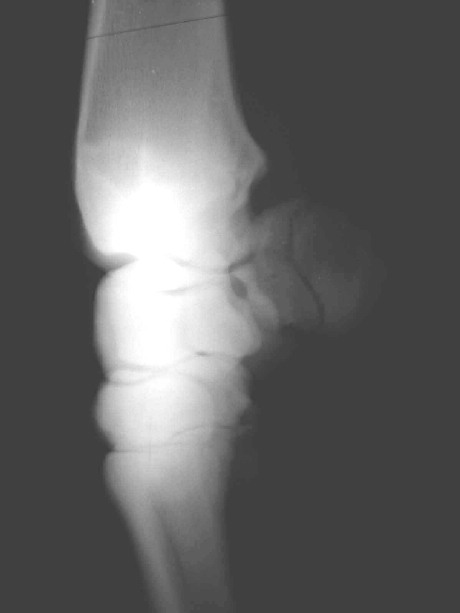

Griffelbeinfraktur

Entfernung der Splitter und Stabilisierung des Gelenksbeteiligten

Teiles mit Zugschraube